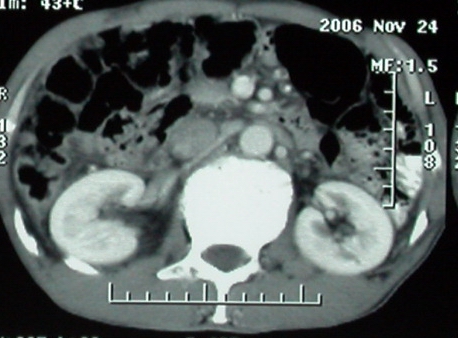

平扫

增强ct所见【动脉增强期】

【病例摘要】男,57岁,农民。因反复上腹部隐痛不适、消瘦2-月就诊。2006年10月初自觉剑突下隐痛不适,放射至背心,早餐和午餐进食正常,晚餐进食后上腹饱胀,夜间卧位症状加重,无厌油,无畏寒发热,无眼黄尿黄,无呕吐腹泻,无黑大便,上述症状反复发作,体重逐渐减轻(体重下降约10kg)。2006年11月22日在卫生院做胃镜检查提示“食道前壁静脉曲张”,超声检查提示“肝脏占位”,2006年11月25日在当地县人民医院ct检查提示“右肝后叶上段占位、左肝萎缩、胆囊肿大、(肝门部?)占位”,超声检查提示“胆囊肿大、胆囊内无结石,(肝门部?)占位、其内有血流信号、似有包膜,下腔静脉受压、门静脉增粗(直径1.9cm)、右肝右叶上段占位、左半肝萎缩、肝内外胆管未见明显扩张、脾脏不大,肠间有少量腹水。”其他辅助检查血常规hb130g/l plt 13万 wbc 14000;肝功能ggt akp显著升高,alt ast轻度升高,胆红素正常,alb 36g/l a/g=1;乙肝两对半表面抗体阳性余阴性。